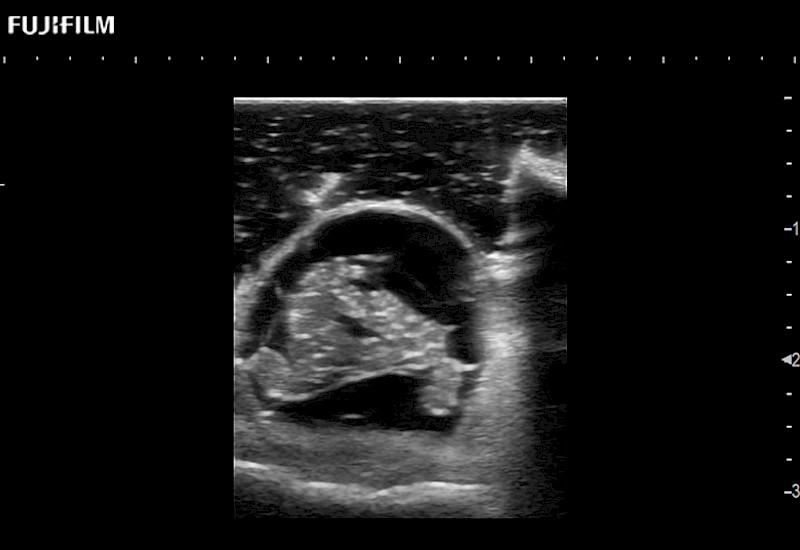

Extraordinary high-resolution digital imaging

for use during: Cranial guidance, Burr-Hole guidance, Spinal Cord guidance, Pituitary guidance, Micro-Surgery guidance

Our dedication to neurosurgery allows us to offer superior image quality, outstanding system reliability and intuitive use of cutting edge technology.